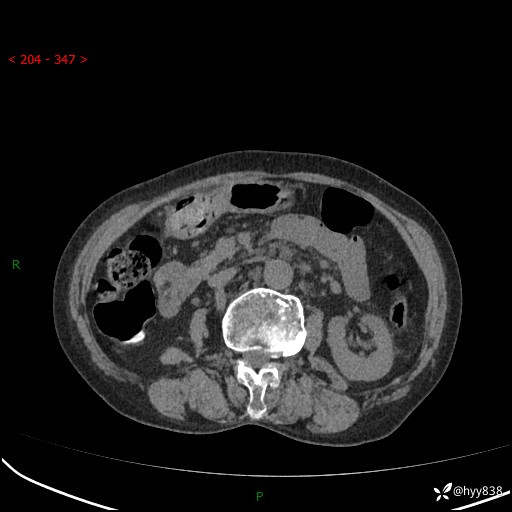

全腹部CT平扫